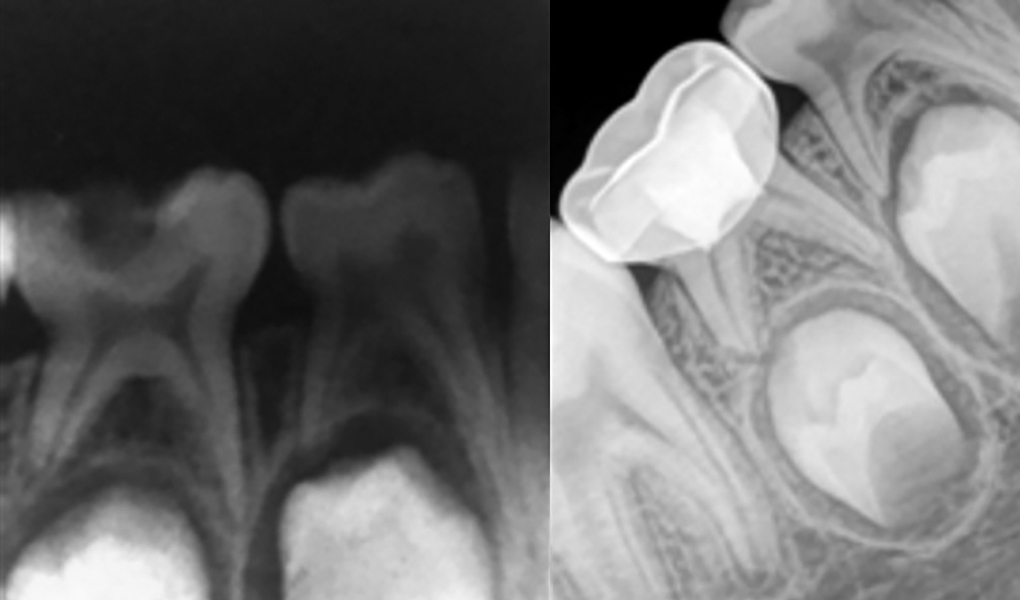

Access opening for pulpotomy procedure 36, 37. Openi Electrosurgical Pulpotomy Procedure Although pulpotomy procedures have a long history of clinical application, comparatively few dental clinical trials have evaluated this. Pulpotomy is one of the most common treatment modalities in pediatric dentistry where amputation of only coronal pulp is done. Radicular pulp remain untouched and treated. The purpose of this study was to observe retrospectively the results of the electrosurgical pulpotomy technique. Electrosurgical Pulpotomy Procedure.

MTA pulpotomy in a primary lower molar. a Clinical examination showing Electrosurgical Pulpotomy Procedure This paper provides a narrative review on the pulpotomy procedure in primary teeth over time, with reference to advances in technique,. Pulpotomy is one of the most common treatment modalities in pediatric dentistry where amputation of only coronal pulp is done. The purpose of this study was to observe retrospectively the results of the electrosurgical pulpotomy technique used on primary. Electrosurgical Pulpotomy Procedure.